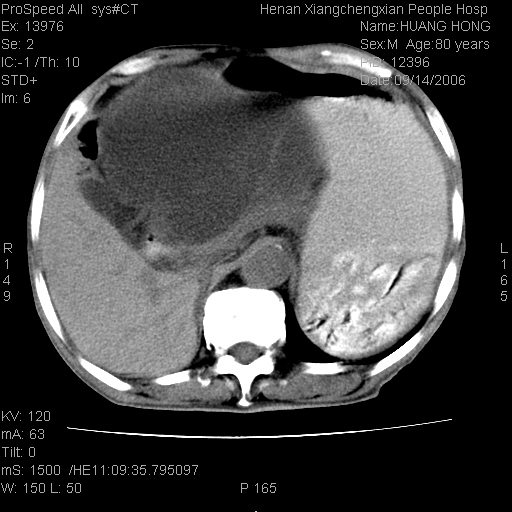

患者, 男, 80岁, 发现上腹部包块1年余,无其它不适.2006-9-14ct片是喝水后扫描2006-9-15ct片没喝水扫描![]() ![]() ![]() ![]() ![]() ![]() ![]() ![]() ![]() ![]() ![]() ![]() ![]() ![]() ![]() ![]() 以上是喝水片 以下是空腹片 ![]() ![]() ![]() ![]() ![]() ![]() ![]() ![]() ![]() ![]() ![]() ![]() ct:胰腺前方、肝脏与胃之间可见巨大类圆形囊性低密度影,大小约152mmx145mmx118mm,上缘平t11椎体上缘,下缘平l3椎体下缘,密度均匀,ct值15hu,其内呈多房分隔,囊壁薄且光滑,边界清晰,周围组织及器官明显受压。肝脏实质内未见异常密度影,胆囊未见异常,胰腺密度未见异常,脾脏大小、形态及密度未见异常,腹膜后间隙未见肿大淋巴结影。 印象:胰腺前方、肝脏与胃之间巨大类圆形囊性低密度影.性质待定。多考虑:.肠系膜巨大囊肿。 守望可可西里发言:支持楼主,考虑肠系膜囊肿,多为小肠系膜。 ysxyy发言:我总觉得这个病人虽然很像肠系膜囊肿,但还是应该强化一下; 下面这几幅图里肿块和主动脉的关系不太清,不知能否除外血管性来源? ![]() ![]() ![]() 病理结果:横结肠系膜间叶瘤.部分区域间质细胞增生活跃. 病理图片 ![]() 良性间叶瘤:是指由两种或两种以上的间叶组织所构成的混合性肿瘤.肿瘤仅发生在腹膜后和肠系膜,.前者较后者多发.良性间叶瘤常发生在肾或四肢,腹膜后较少见,各年龄均可发病.女多与男,预后较好,但术后易复法. 恶性间叶瘤:由两种以上恶性间叶组织成分组成. 光镜:肿瘤由脂肪/血管/平滑肌构成. 原贴地址: http://www.radinet.com.cn/forum_view.asp?forum_id=4&view_id=16217 ok |